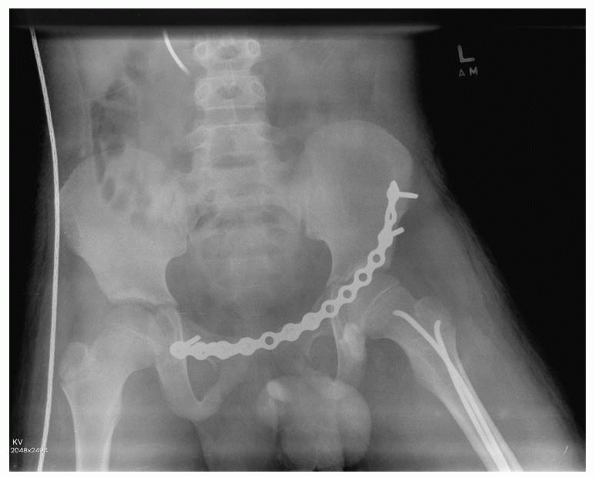

![]() |

FIGURE 20-18 A.

Multiple trauma in this 12-year-old child included three fractures of the pubic rami, disruption and fracture of the sacroiliac joint on the right, and a femoral shaft fracture on the right. B. CT shows fracture of the ilium and disruption of the sacroiliac joint. C. After open reduction and internal fixation of the sacroiliac joint and closed intramedullary nailing of the femoral shaft fracture. Note femoral nail inserted through the tip of the greater trochanter. |

sacroiliac screws. Insertion of sacroiliac screws requires expertise

Then a fluoroscopic 40-degree pelvic inlet and 40-degree pelvic

outlet views are obtained to direct the guidewire across the sacroiliac joint into the body of S1(Fig. 20-20).

One 6.5-mm cannulated screw is optimal. In the pediatric patient, the